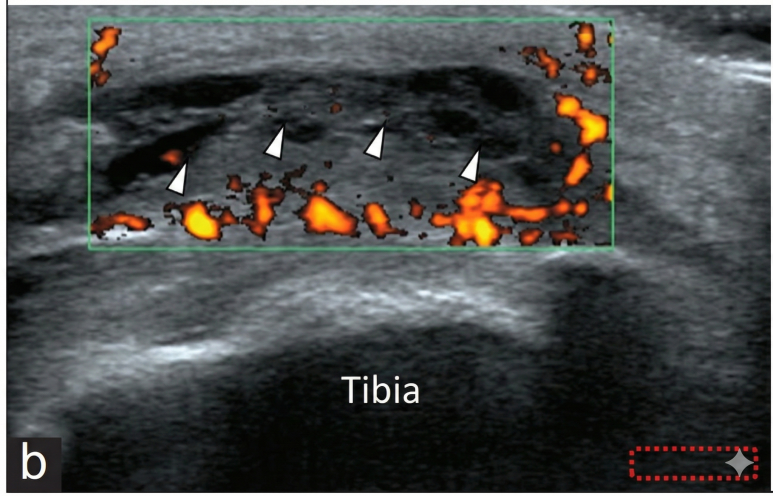

이 논문에서는

무릎 앞쪽이 붓고 아픈 환자를

초음파로 진단했습니다.

논문의 초음파 영상을 보면

피하층에 까맣게 물이 고여 있고

그 주변으로 혈류가 증가해

빨갛게 보이는 염증 소견이 확인됩니다.

그리고 여기서 중요한 핵심은

이 점액낭(물주머니)은통증 수용체가 아주 발달해 있어서,염증이 생기면 극심하게 아프다는 겁니다.